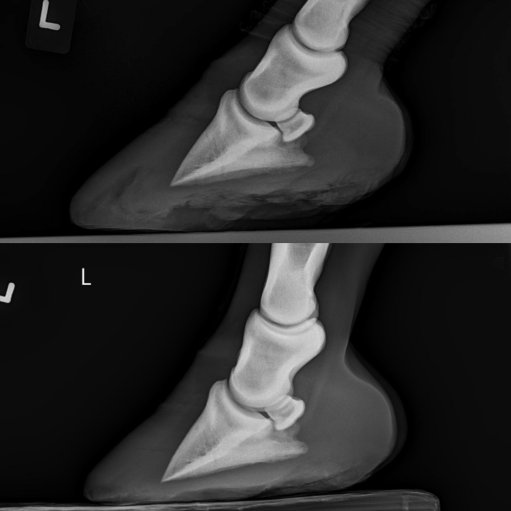

But her x-rays and feet went from looking like this:

To looking like this:

You can bet I’m feeling pretty damn good about that. Just a big breath of relief. Looks like we’ve found a perfect angle, and having shoes on the hind feet and a pad is all just the right mix for her. That’s A LOT of sole that she grew, which is super positive. Even Doc said that in all her x-rays she’s never grown this much hoof, which is excellent. A definite “yes” that we’re on the right track again! I know she’s happy – she really really hated those boots lol.

Doc also said that she’ll probably have a very normal-looking foot. While that’s a plus, I’m certainly not too worried even if it’d look abnormal. It’d just get trimmed in the way it functioned the best. It’s still a positive, though, so you can bet that I’m taking that too haha! Her front feet are looking positive as well, and I think she’s a lot more comfortable.